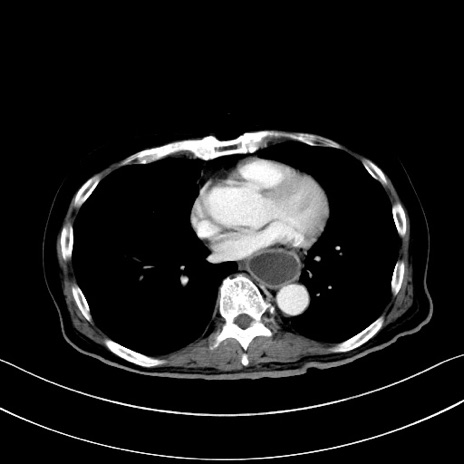

症例28(横断像)

【症例】60歳代男性

【主訴】嘔吐

【現病歴】胃癌にて胃全摘後。食思不振が悪化し、夜中に嘔吐することがある。

【既往歴】胃癌、胃全摘、脾摘、胆摘後

【データ】WBC 5900、CRP 10.56